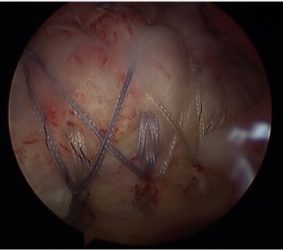

Arthroscopic image of rotator cuff tear.

Appearance after repair